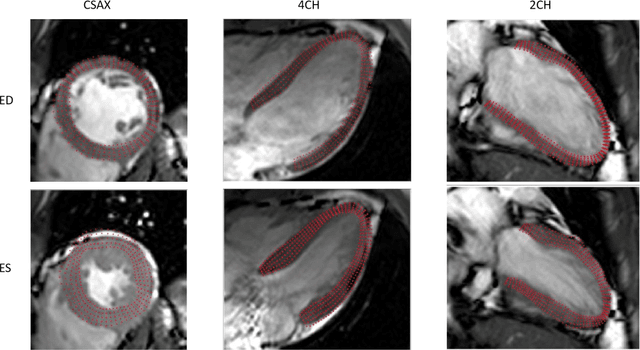

Abstract:In this paper, we propose an enhanced 3D myocardial strain estimation procedure which combines complementary displacement information from multiple orientations of a single imaging modality (untagged CMR SSFP images). To estimate myocardial strain across the left ventricle, we register the sets of short-axis, four-chamber and twochamber views via a 2D non-rigid registration algorithm implemented in a commercial software (Segment, Medviso). We then create a series of interpolating functions for the three orthogonal directions of motion and use them to deform a tetrahedral mesh representation of a patient-specific left ventricle. Additionally, we correct for overestimation of displacement by introducing a weighting scheme that is based on displacement along the long axis. The procedure was evaluated on the STACOM 2011 dataset containing CMR SSFP images for 16 healthy volunteers. We show increased accuracy in estimating the three strain components (radial, circumferential, longitudinal) compared to reported results in the challenge, for the imaging modality of interest (SSFP). Our peak strain estimates are also significantly closer to reported measurements from studies of a larger cohort in the literature. Our proposed procedure provides a fast way to accurately reconstruct a deforming patient-specific model of the left ventricle using the commonest imaging modality routinely administered in clinical settings, without requiring additional or specialized imaging protocols.